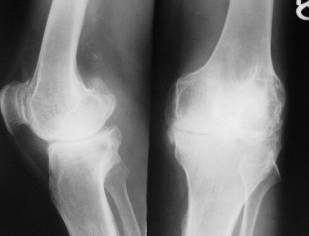

GONARTROZA se întâlneste mai frecvent la femei, dupa menopauza. Este secundara când apare dupa leziuni preexistente: genum valgum, varum, luxatie congenitala de sold, traumatisme ale genunchiului.

Radiologic: reducerea spatiului articular si osteofite. Ele se evidentiaza pe radiografia de profil. La nivelul articulatiei femuro-tibiale se evidentiaza pensarea inegala a articulatiei, derotunjirea suprafetelor articulare, largirea si alungirea spinelor tibiale prin osteofite, scleroza suprafetelor articulare, aparitia de formatiuni pseudochistice în platourile tibiale, osteofite.